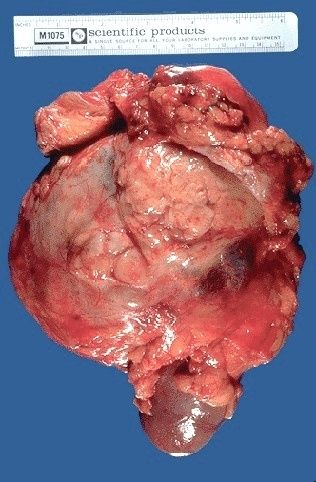

| Tumor de Wilms |

Image:

Renal057 (image/jpeg)